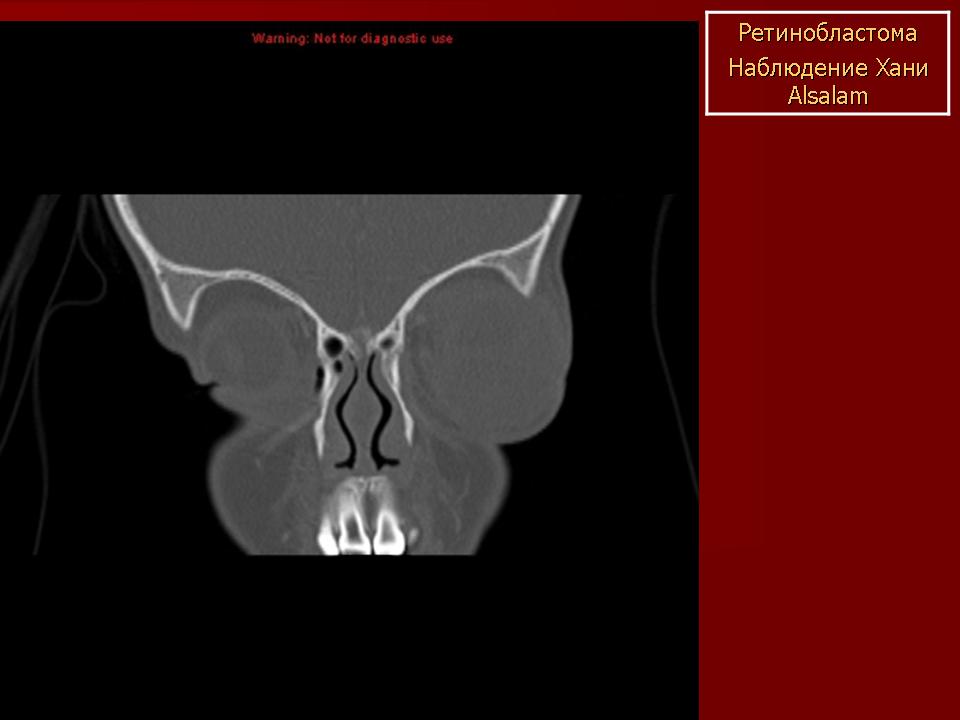

Наиболее характерный признак: внутриорбитальное объемное образование, содержащее обызвествления. Солидное образование сетчатки с центральной локализацией в задней части глазного яблока. Типично умеренное или интенсивное накопление КВ. Часто сочетается с неспецифической отслойкой сетчатки.

Ретинобластома может прорастать экстраорбитальные структуры по ходу зрительного нерва; через отверстие зрительного нерва опухоль может проникать в полость черепа или орбиту. В редких случаях сочетается с опухолями гипофиза или супраселлярной области.

Ретинобластома имеет вид мягкотканного объемного образования с наличием типичных точечных обызвествлений (менее 90%).

По данным КТ выделяют 3 степени роста ретинобластомы.

I степень – опухоль располагается внутри глазного яблока, часто содержит мелкие кальцинаты, плотность не увеличивается после контрастирования;

II степень – в процесс вовлечены ретроорбитальные ткани и зрительный нерв, края глазного яблока нечеткие, кальцинаты встречаются редко;

III степень – процесс выходит за пределы глазницы, опухоль хорошо конграстируется, кальцинаты не встречаются.